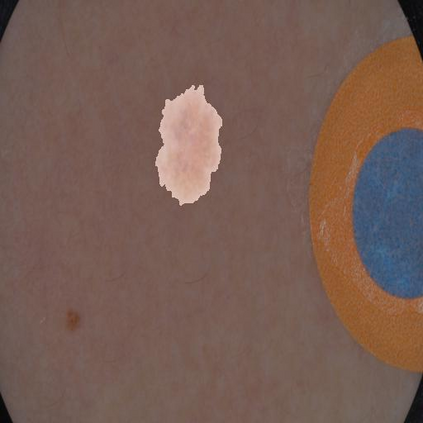

Skin lesion segmentation from dermoscopy images is of great significance in the quantitative analysis of skin cancers, which is yet challenging even for dermatologists due to the inherent issues, i.e., considerable size, shape and color variation, and ambiguous boundaries. Recent vision transformers have shown promising performance in handling the variation through global context modeling. Still, they have not thoroughly solved the problem of ambiguous boundaries as they ignore the complementary usage of the boundary knowledge and global contexts. In this paper, we propose a novel cross-scale boundary-aware transformer, \textbf{XBound-Former}, to simultaneously address the variation and boundary problems of skin lesion segmentation. XBound-Former is a purely attention-based network and catches boundary knowledge via three specially designed learners. We evaluate the model on two skin lesion datasets, ISIC-2016\&PH$^2$ and ISIC-2018, where our model consistently outperforms other convolution- and transformer-based models, especially on the boundary-wise metrics. We extensively verify the generalization ability of polyp lesion segmentation that has similar characteristics, and our model can also yield significant improvement compared to the latest models.